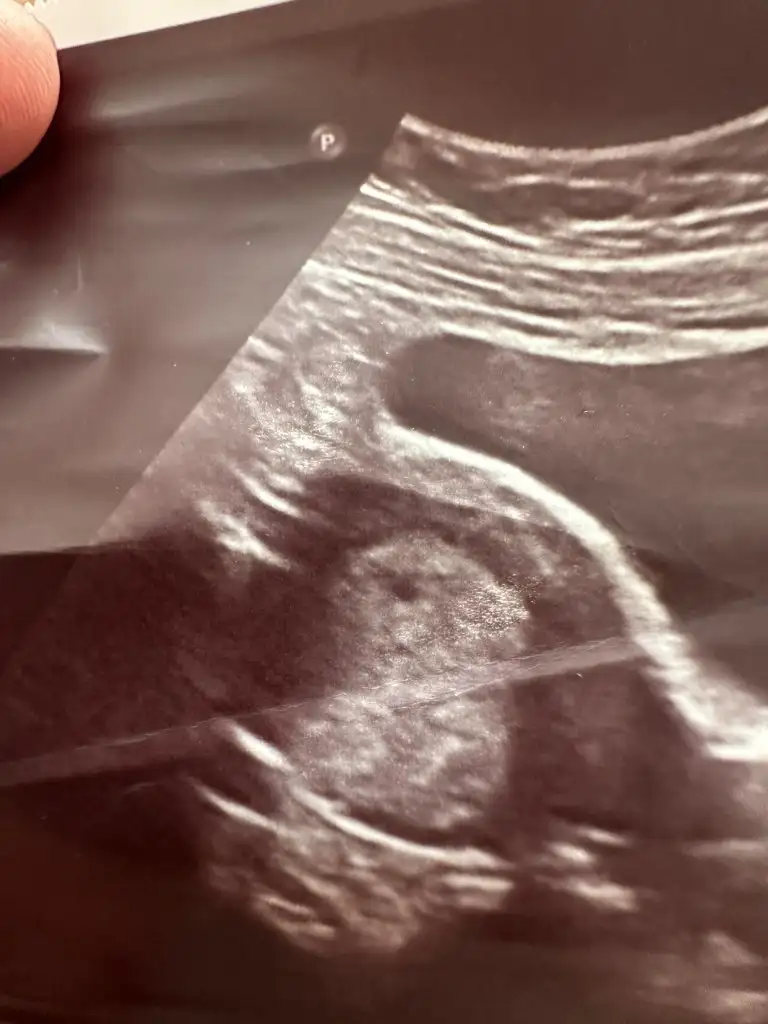

Yaa çok iyi olur 4. Haftada görünür diyolar ama bilemedim :)Kızlar keselerını goren dostlarımız atsada baksakbıde kac artı kacta gorduklerını yazsalar.hem grup hareketlenır

Benımkı 4+5 te gozuktu kuzum karından ama yumurtlama gunumu bılıyordum tam son adet tarıhıyle uyumlu cıktı.ama cok merak edıyorum kese fotograflarınıYaa çok iyi olur 4. Haftada görünür diyolar ama bilemedim :)

Yaaaa minicikBenımkı 4+5 te gozuktu kuzum karından ama yumurtlama gunumu bılıyordum tam son adet tarıhıyle uyumlu cıktı.ama cok merak edıyorum kese fotograflarınıböyle mınıcık bıseydı

Ayy kuzum hoşgeldinnn öncelikle çok ama çok sevindim sağlıcakla gelsinBasakbasak1 edahandro napıyosunuz kuzularımm bebısler kac aylık olduu başaaak geriden katıldım ama katıldım kervana bu cumartesı keseyı gordum ,6+1 de bıda gıtcem cumartesı gunu kalbı duyulurmu sızce bıde agzımdan yara cıktı ne yapıyım sızce